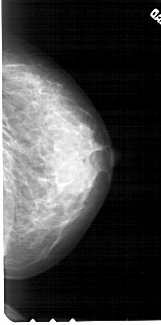

A_1783_1.LEFT_MLO

LEFT_MLO LINES 5491 PIXELS_PER_LINE 2671 BITS_PER_PIXEL 12 RESOLUTION 43.5 OVERLAY